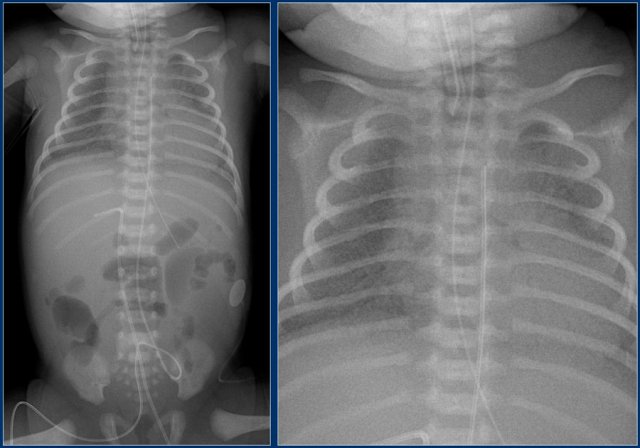

Umbilical artery line (2)

First study the images.

Then continue reading.

The findings are:

1. Umbilical artery line in a good high position.

2. Malposition of umbilical vein line in right portal vein.

3. Skin folds over right basal thorax, which should not be mistaken for a pneumothorax. They typically do not follow anatomical borders.